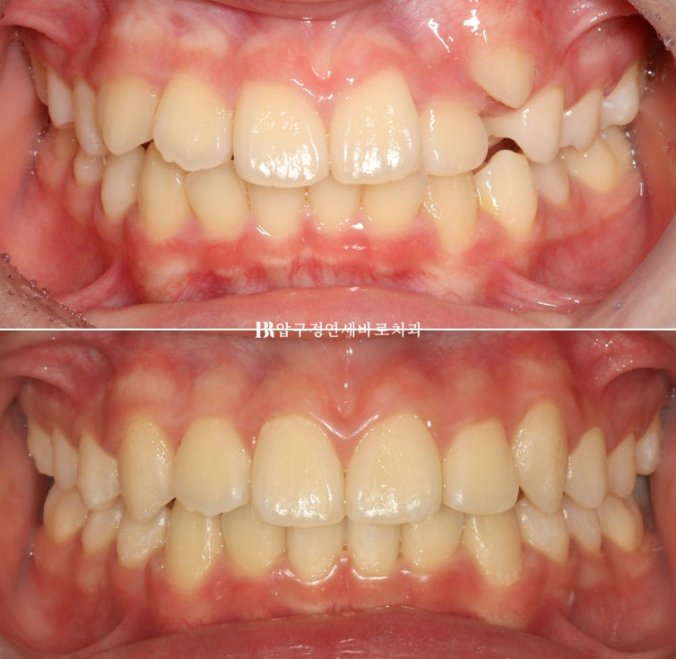

덧니가 있어서 내원한 학생입니다.

덧니를 고치고 싶어서 내원을 하였지만, 위 아래 중심선도 맞지 않는 것이 보입니다.

덧니 공간을 마련하고 송곳니를 배열했습니다.

덧니가 온전히 제자리를 찾았습니다.

장치 제작기간을 제외하고 실제로 덧니 인비절라인 교정 장치 긴 기간은 1년 입니다.

치료 전 후 자료입니다.